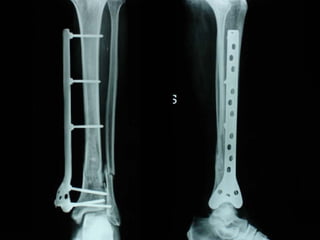

Dal Gennaio 2000 al Febbraio 2006 abbiamo trattato 167 fratture chiuse  con placca percutanea  in 164 pazienti :  27 lesioni diafisarie di gamba, 12 piloni tibiali ,  11 fratture prossimali di tibia, 36 fratture sovracondiloidee di femore, 17 fratture diafisarie di femore, 43 fratture metaepifisarie prossimali di omero, 21 diafisarie d’omero.  156 guarigioni 8 fallimenti

Dal Giugno 2002 al Dicembre 2004 abbiamo trattato 5 fratture esposte: 3 di tibia e 2 di ulna 5 guarigioni

I buoni risultati ottenuti dipendono da 5 punti fondamentali:   una accurata riduzione percutanea della frattura  precise vie di accesso  l’utilizzo della placca che consenta il più lungo braccio di leva possibile il pretensionamento della placca  una sintesi con un ridotto numero di viti

Placche lunghe e pretensionate

Placche lunghe e pretensionate Sintesi con un ridotto numero di viti